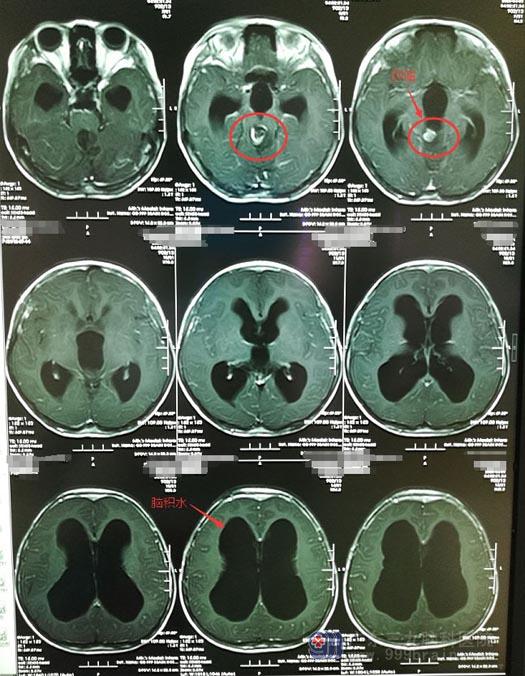

近一个月来,小茵又出现间断的头痛头晕症状,同时伴有呕吐。敏感的小茵父母立马带着她来到广东三九脑科医院复查,结果发现术区中脑导水管残留病变较前增大,病变大小约1.4cm×1.5cm×1.6cm,伴有梗阻性脑积水。

入住神经外五科后,小茵出现反复头痛及恶心,呕吐,考虑重度脑积水。颅内压力高,对于她来说就是一种高风险,很容易随时发生脑疝,造成生命危险。神经外五科治疗团队决定急诊为她行脑室外引流术,先降低压力、缓解头痛症状。